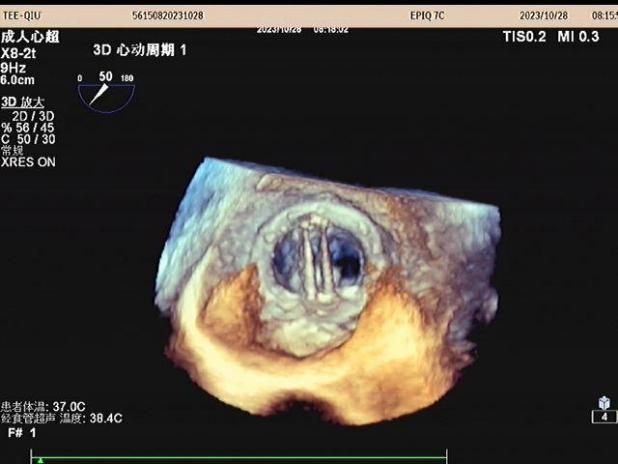

经食道超声心动图三维图像清晰显示房间隔、二尖瓣机械瓣

3、人工瓣膜功能评价,如二尖瓣、主动脉瓣人工瓣膜置换术后,有无瓣周漏、梗阻等。